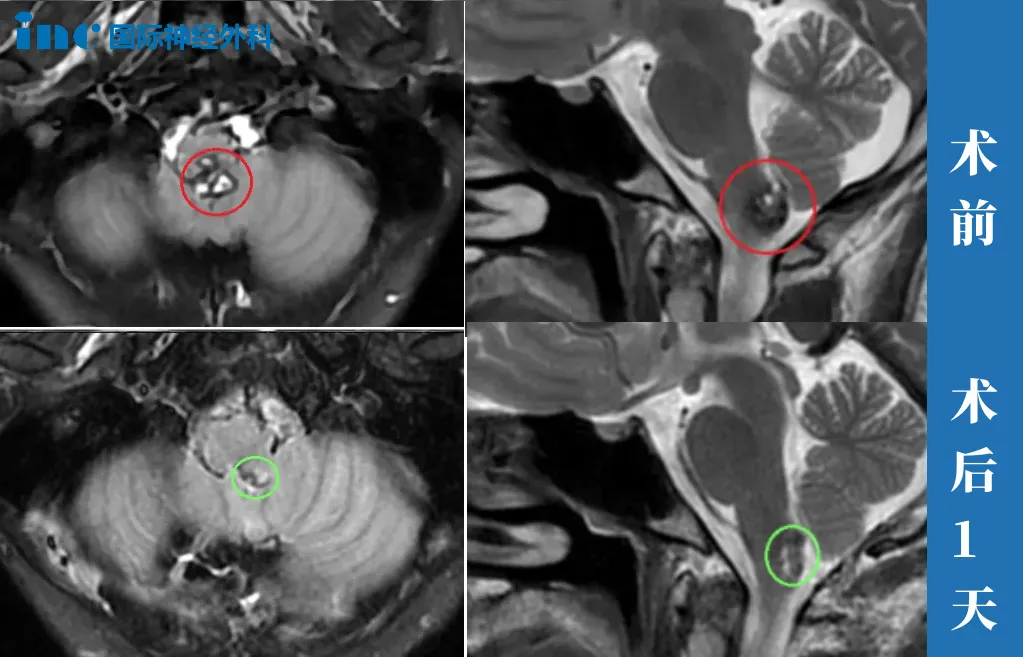

12岁女孩—脑干海绵状血管瘤

“刚开始的时候,只以为是一个流感。后面孩子已经变得很严重了,整个半身已经出现瘫痪的状态。120急救,送到儿童医院。脑干出血,医生说,这个过程其实是凶险的,因为孩子随时都有可能“走掉”。

我们是安排了早上一台手术,手术当天晚上,然后医院里安排我们跟她做了一个视频的,这个可以去视频看看他。她也能讲话了,所以我们那个时候就已经开心了,二天就出ICU了。你看我们小朋友今天这个各方面恢复的特别特别的好,所以特别感谢巴教授。”